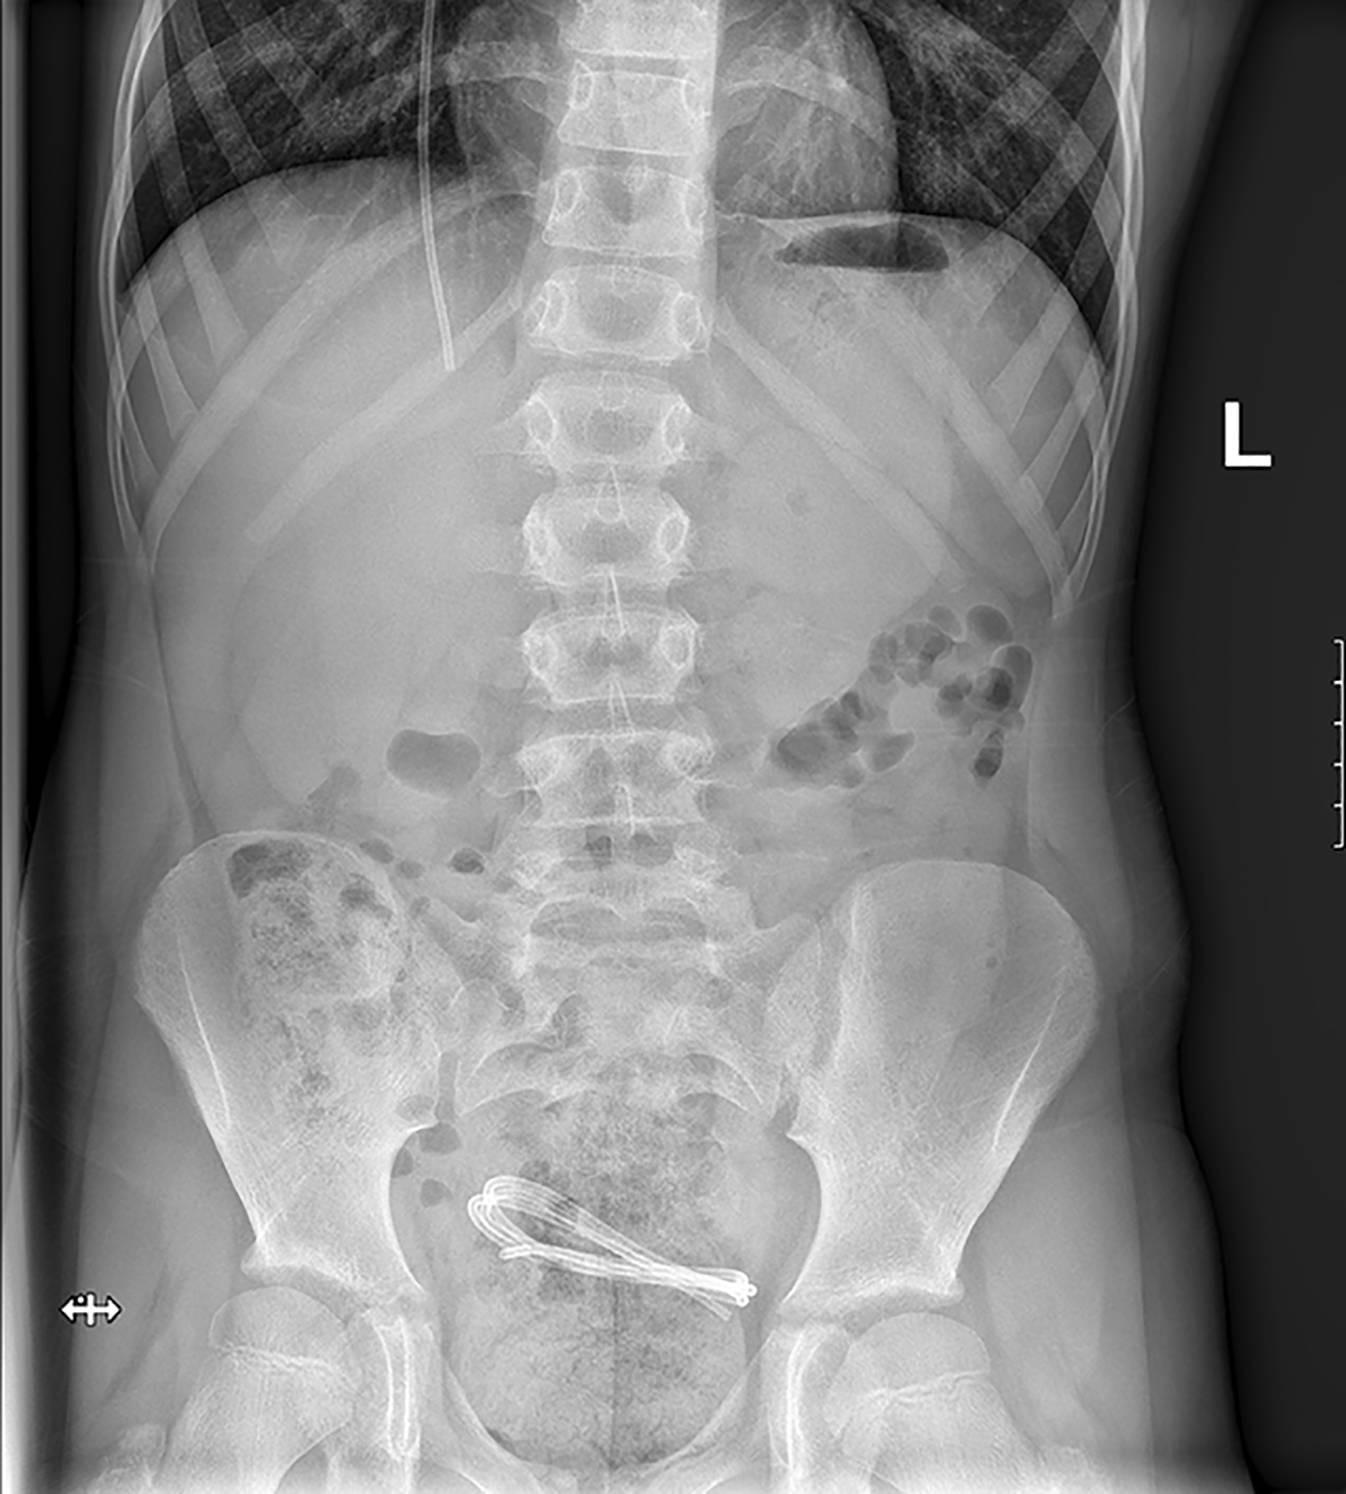

Ein 11-jähriger Junge mit posttraumatischem VP(ventrikuloperitonealem)-Shunt stellte sich bei neu aufgetretenen fokalen Krampfanfälle in unserer Notaufnahme vor. Die Abdomenübersicht ist abgebildet (Abb. 1) – die Diskonnektion in Höhe des Brustwirbelkörpers (BWK) 12 ist gut erkennbar.

Abb. 1

Röntgen Abdomen stehend p. a. ; Diskonnektion und Schlauchende dargestellt